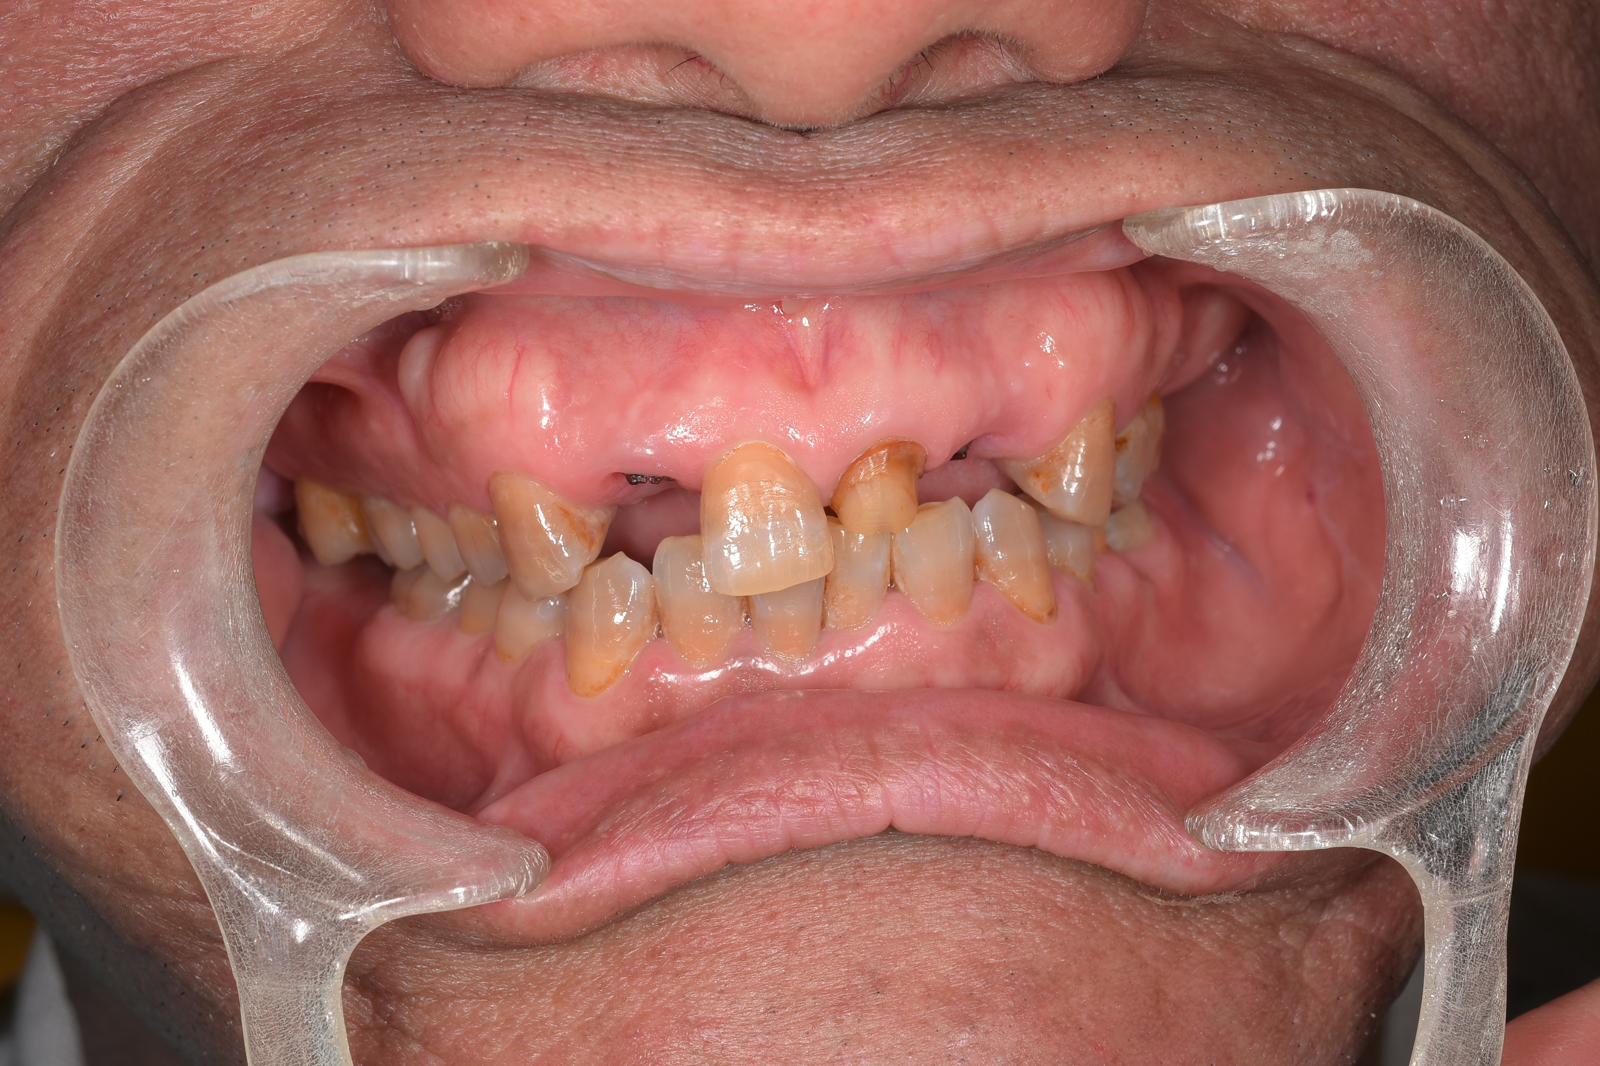

重度の虫歯で失われた、上あご全体の歯を包括治療した症例。